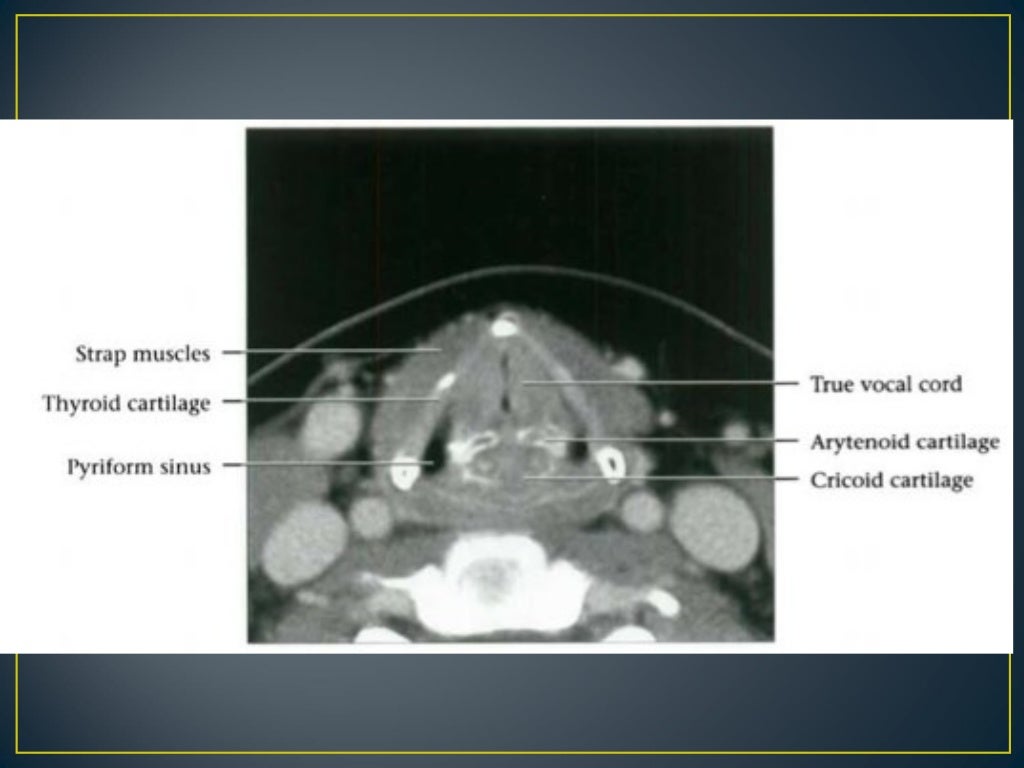

Ct Anatomy Of The Larynx . 21 articles feature images from this case. The purpose of this article is to briefly review currently used imaging protocols, key anatomic structures in the larynx and hypopharynx. The larynx consists of a cartilage skeleton, as well as internal structures that are divided into three subsites, mainly for the purposes of laryngeal cancer. Scrollable ct highlighted the anatomy of the neck. 152 public playlists include this case. Ct is the preferred modality for laryngeal trauma, as it can be performed more simply than mri in the acute or immediate subacute clinical. This article focuses on the use of ct imaging in the evaluation of the larynx, with particular focus on laryngeal neoplasia, trauma,.